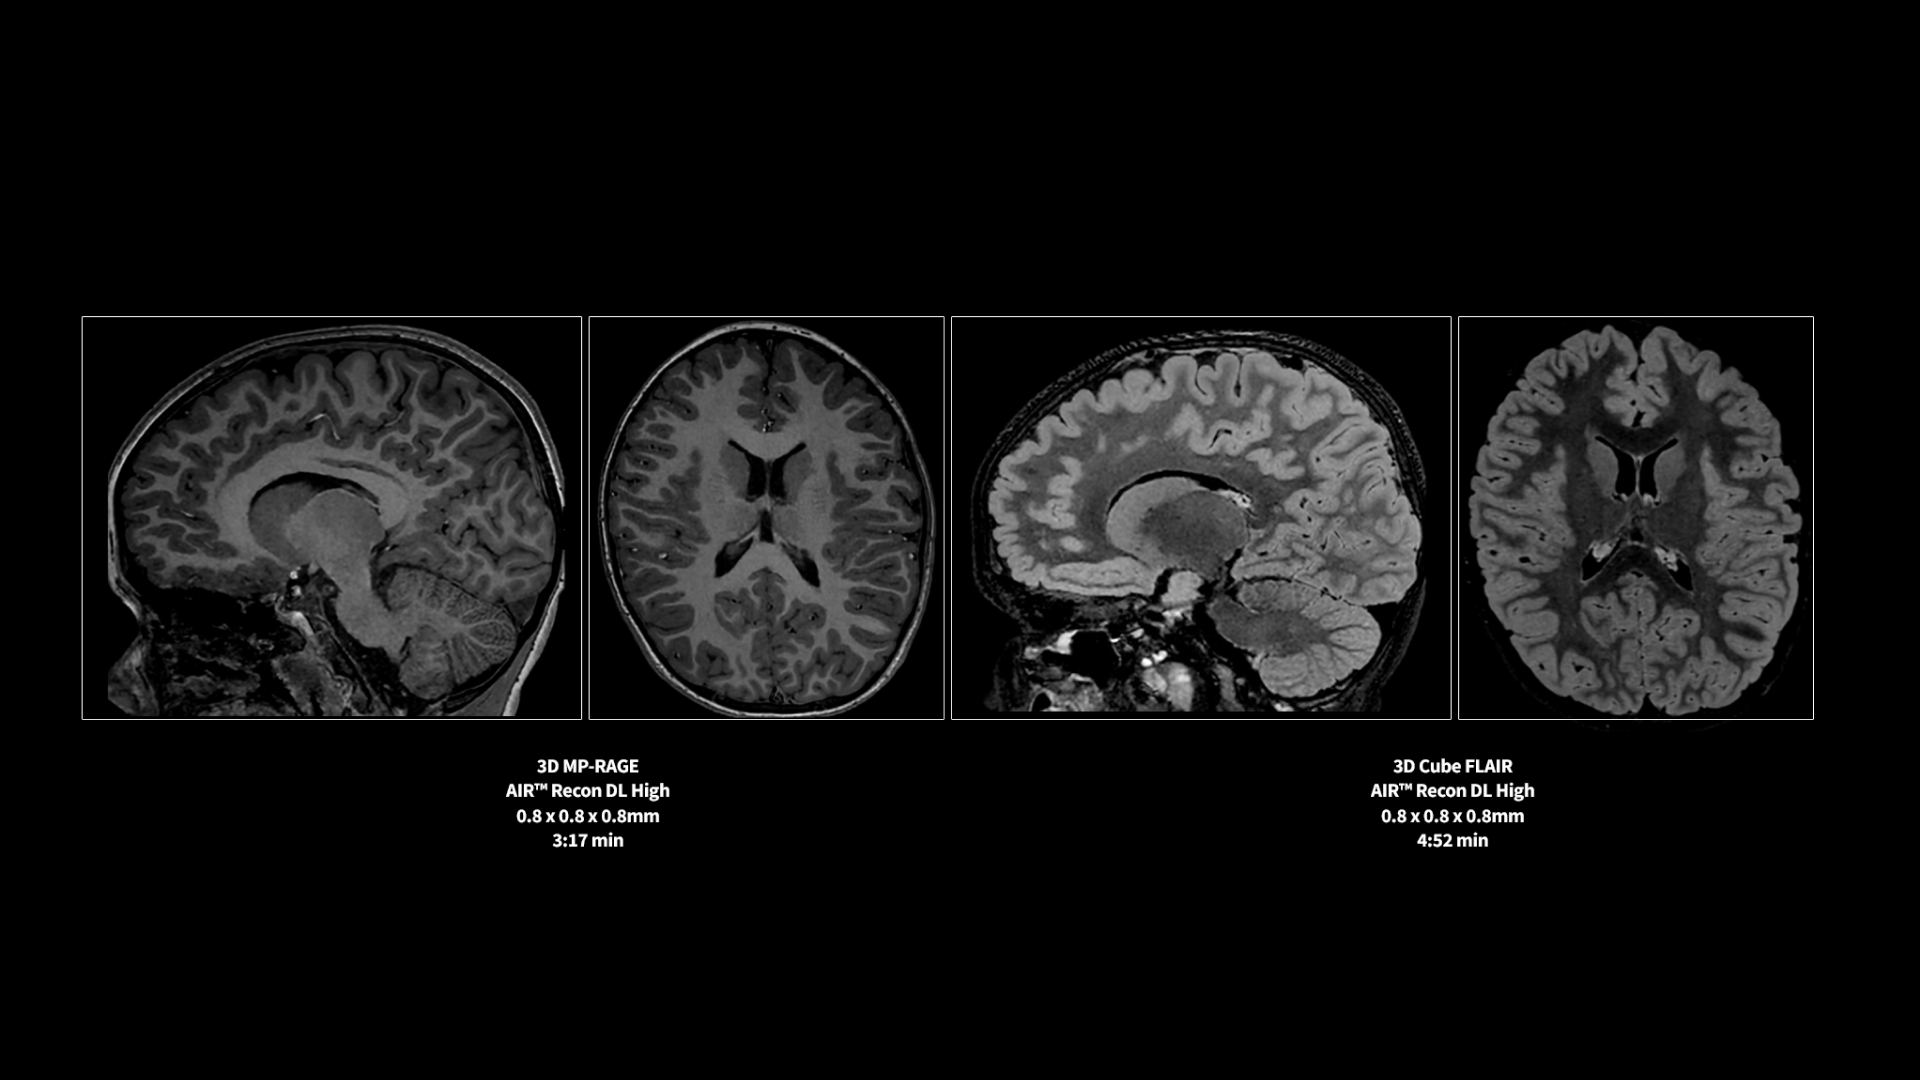

Revolutionary, deep-learning-based reconstruction techniques such as AIR™ Recon DL provide sharper, clearer, and accurate images

Pin-sharp image quality and exceptional speed with AIR Recon DL and Sonic DL​

Experience pin-sharp precision and remarkable speed with a 3T SIGNA Premier MRI scanner, coupled with AIR Recon DL and Sonic DL™.